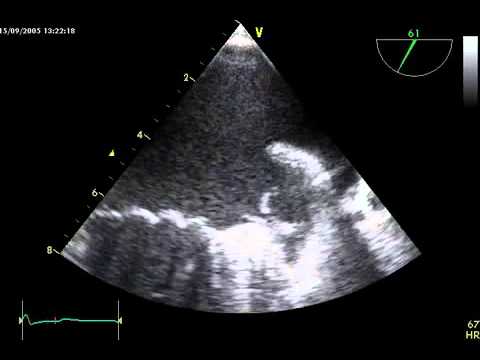

Video 16.3

Video 16.3 Echocardiographic exclusion of alternative cardioembolic sources.